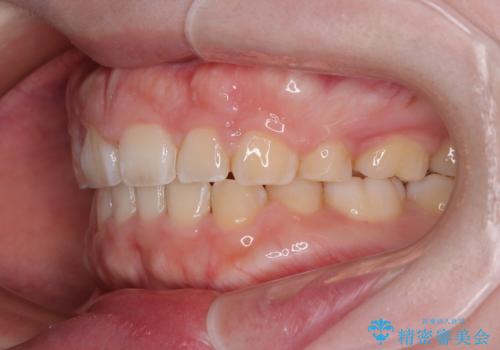

- 出っ歯と口の閉じにくさ、デコボコを気にして来院された患者様です。

口元の突出感を改善するため、上下左右第一小臼歯4本の抜歯を行い、ワイヤー装置による矯正治療を行うこととしました。

抜歯矯正を行ったことで、顎先のつっぱり感や口元の閉じにくさを解消することができました。